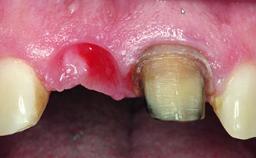

A 32-year-old female Caucasian patient with a compromised maxillary right central incisor was referred to us by a general dentist. Her chief complaints were discomfort and mobility of tooth 11 with unsatisfactory esthetics due to discoloration. The patient reported a previous trauma, some years earlier, as the origin of pathology on the afflicted tooth. Anamnesis was negative for any other dental or periodontal pathology in the remaining dentition. The patient did not take any medication and reported to be a light smoker (5–10 cigs/day). She had high esthetic expectations of her treatment. The extraoral examination revealed a high smile line with full exposure of her maxillary teeth and surrounding soft tissue in the area between the second premolars.

Bone Augmentation Horizontal|Simultaneous|Staged

Soft Tissue Grafting Staged